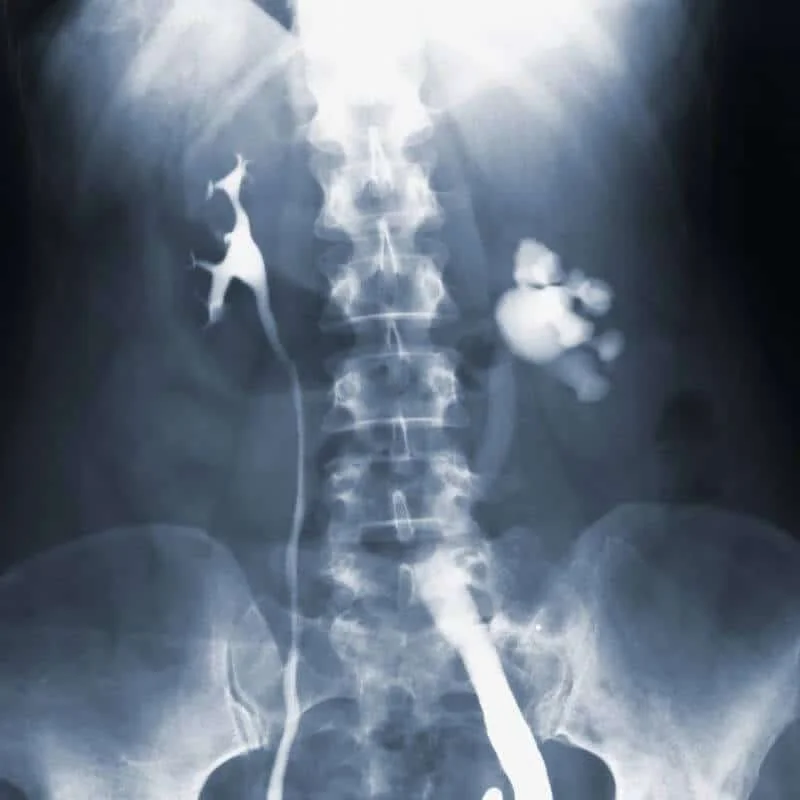

RADIOGRAFÍA DE COLUMNA LUMBAR

La radiografía de columna lumbar es un examen de diagnóstico por imagen que emplea rayos X para generar una representación detallada de las estructuras internas de la parte baja de la columna vertebral.

Este procedimiento emplea una máquina de rayos X, compuesta por un generador y una placa de imagen. Durante el examen, el generador emite un haz de rayos X que atraviesa la columna lumbar. Al interactuar con el cuerpo, los rayos son absorbidos en mayor o menor medida según la densidad de los tejidos: los huesos, por ser más densos, aparecen en tonos claros; mientras que los tejidos más blandos se ven en sombras más oscuras en la imagen.

Adicionalmente, este examen permite observar anomalías como curvaturas irregulares de la columna, signos de desgaste en los huesos y el cartílago, tales como espolones óseos o estrechamiento de los espacios articulares.

También puede detectar fracturas, signos de osteoporosis (pérdida de densidad ósea) o espondilolistesis, una condición en la que una vértebra lumbar se desplaza fuera de su alineación sobre la vértebra subyacente. Gracias a esta información, los médicos pueden determinar un diagnóstico más preciso, lo que facilita el tratamiento adecuado para mejorar la calidad de vida del paciente.